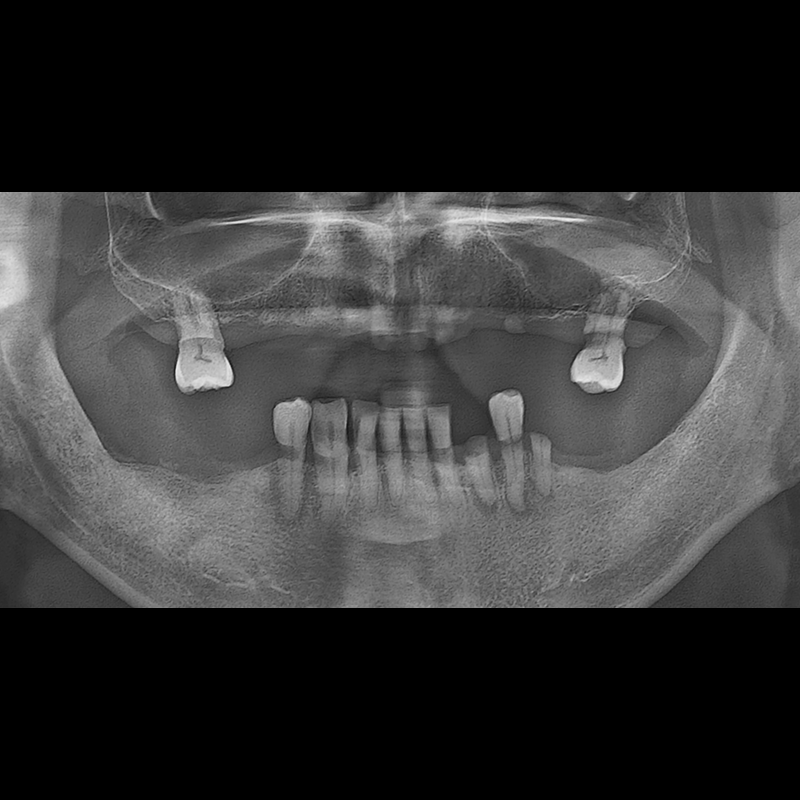

BEFORE AFTER

种植牙前后的照片 2025.05.30

在缺失的牙齿部分和难以挽救的牙齿位置植入了种植牙。